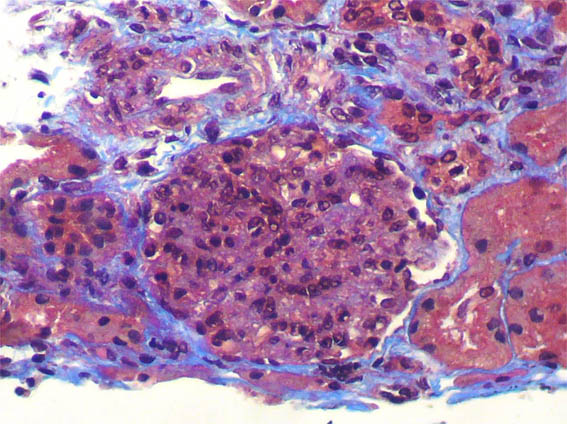

Figura 4.

Tricrómico de Masson, X400.